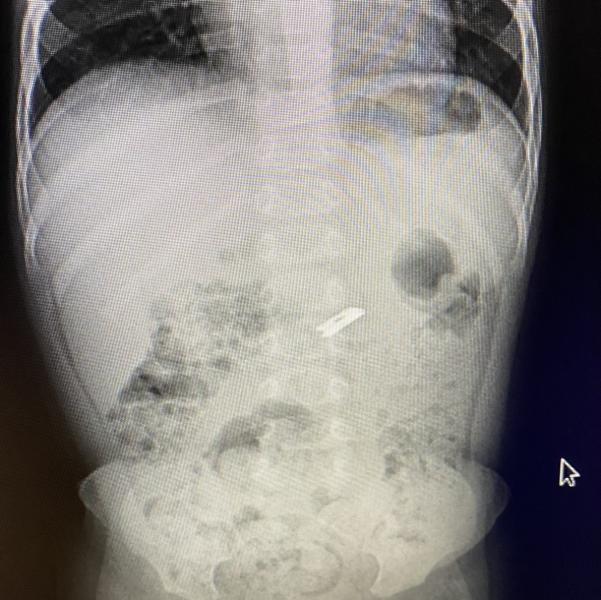

Ребёнок съел железку.

Врачи сказали подождать 5-6 дней

Что это не относится к опасным вещам

Опасные батарейки,магниты